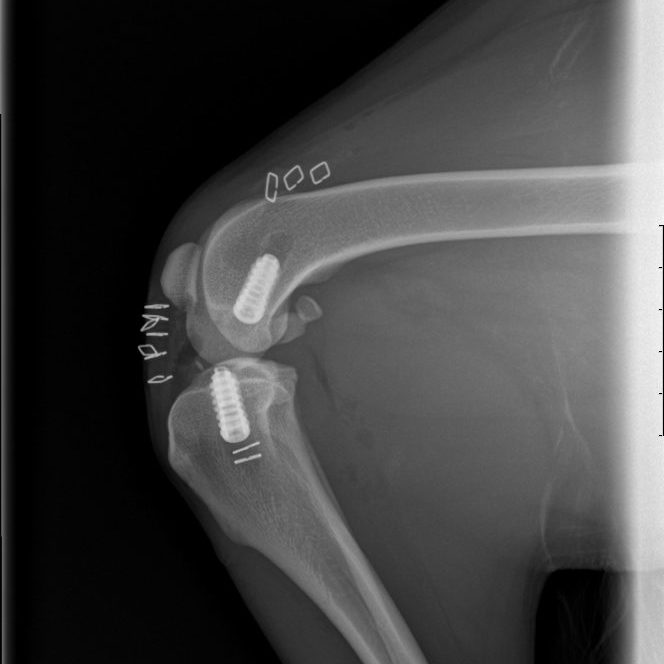

Intra-articular CCL reconstruction Under Construction. Share this post Share on FacebookShare on Facebook TweetShare on Twitter Pin itShare on Pinterest Share on LinkedInShare on LinkedIn Share on WhatsAppShare on WhatsApp Project navigationPreviousPrevious project:Minimally invasive Extra-articular CCL RepairNextNext project:Shoulder